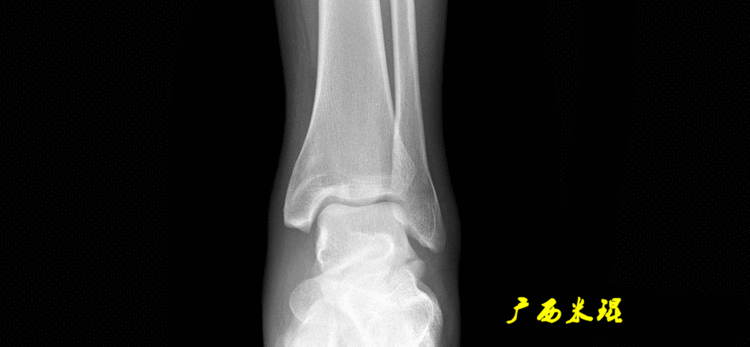

(3)踝关节中心踝关节中心点常用的也有3个,分别是骨骼(内、外踝表面间距)中点、踝关节间隙水平软组织中点和距骨宽度中点。

说明一下,膝关节线常常为膝关节间隙的水平线,也是膝关节的轴线,只有在比较正常的关节情况下使用,大多数情况下画出股骨远端机胫骨近端的关节线更好。(4)踝关节线踝关节线为胫骨远端软骨下骨之间的连线。

胫骨远端外侧角(mLDTA):胫骨远端切线(关节线)与下肢力线(机械轴)两者之间的外侧夹角,正常为89°±3°。